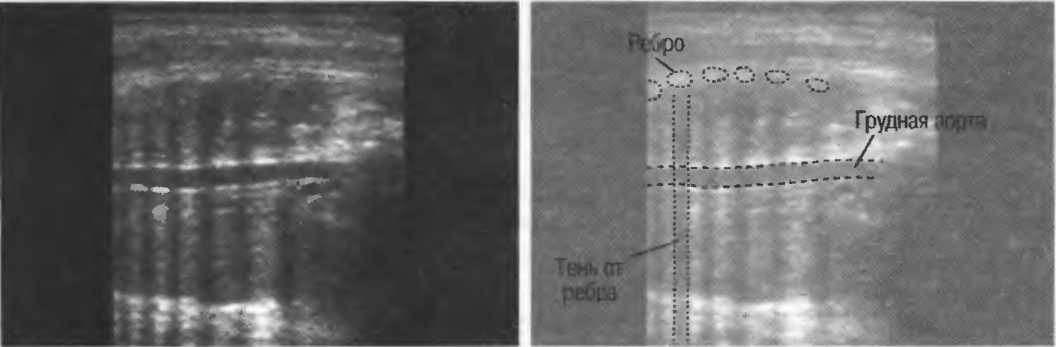

Рис.5. Два поперечных среза плода, демонстрирующих тень от позвоночника плода. Аналогичная тень от ребер может частично закрывать почки или печень. Изменяя угол наклона датчика, можно изменить положение тени таким образом, чтобы подлежащие ткани были видны отчетливо.

Плотные материалы, такие как кости или камни, дают акустическую тень на структуры, расположенные сзади, в результате того что ультразвуковая волна не проходит через них. Этот феномен получил название «акустической тени». Например, ребра могут экранировать ультразвуковой поток, поэтому структуры, расположенные за ними, нужно исследовать в косом направлении по межреберным промежуткам (рис. 10б,в).